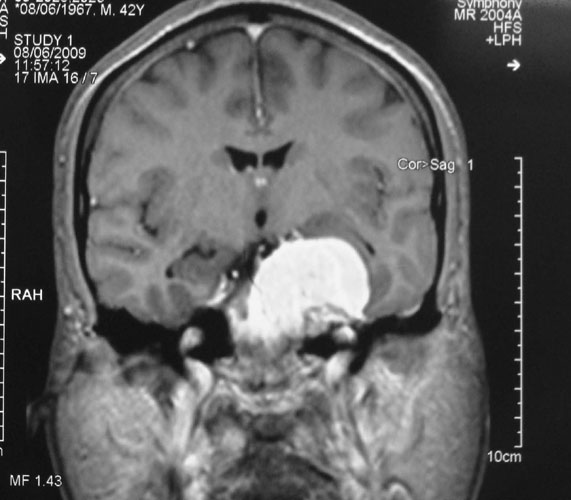

Medulloblastomas

Medulloblastomas are common tumors in childhood, often presenting with vomiting and headache. These tumors are located in midline of the cerebellum (back of the head). Diagnosis is made with MRI, and complete excision can be done safely in majority of the children.